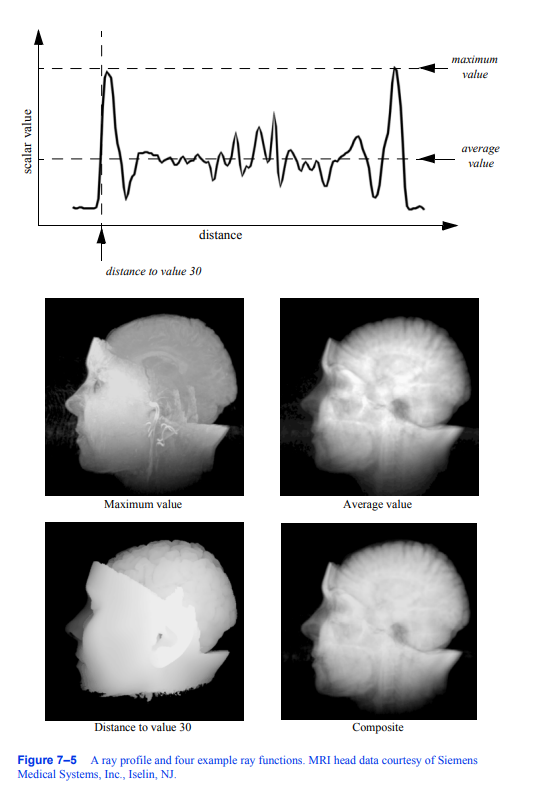

图7 - 5显示了一条射线经过8位体积数据时的数据值剖面,其中数据值的范围在0到255之间。配置文件的x轴表示与视图平面的距离,y轴表示数据值。从四个不同的简单射线函数得到的结果显示在剖面下面。为了显示,我们使用类似于前一个示例中的方法将原始结果值转换为灰度值。

前两个射线函数,最大值和平均值,是标量值本身的基本操作。第三个射线函数计算第一次遇到大于或等于30的标量值时沿射线的距离,而第四个使用alpha合成技术,将沿射线的值视为每单位距离积累的不透明度样本。与前三个射线函数不同,合成技术的结果不是可以在射线剖面上表示的标量值或距离。

最大强度投影(MIP)可能是可视化体积数据的最简单方法。当涉及到有噪声的数据时,这种技术是相当宽容的,并且生成的图像提供了对底层数据的直观理解。这种方法的一个问题是,不可能从静止图像中判断出沿射线的最大值发生在哪里。例如,考虑图7 - 6所示的颈动脉图像。我们无法从这张静止图像中完全了解血管的结构,因为我们无法确定某些血管是在另一些血管的前面还是后面。这个问题可以通过生成显示数据旋转的小图像序列来解决,尽管对于并行摄像机投影,即使这个动画也会模糊。这是由于两个图像生成的相机

图7-5射线轮廓图和四个射线函数示例。MRI头部数据由西门子提供

医疗系统公司,Iselin,新泽西州。